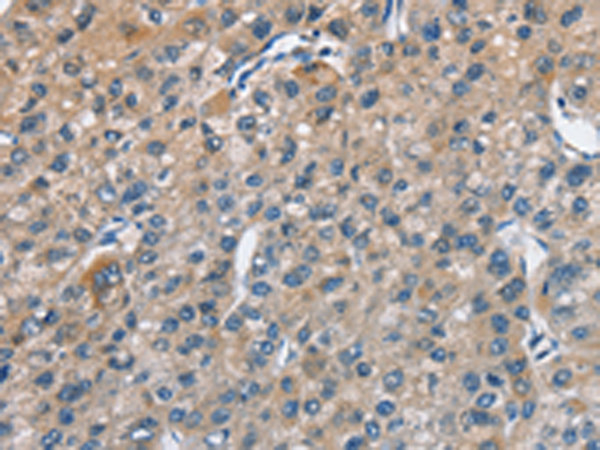

分类: 科研抗体货号: P08016别名: CBR; hCBR1; SDR21C1应用: WB,IHC反应种属: Human, Mouse, Rat